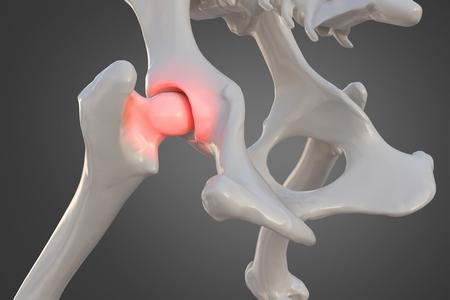

La dysplasie de la hanche chez le chien

Notre focus du jour porte sur la dysplasie de la hanche chez le chien. Touchant généralement les grandes races et les chiens en surpoids, cette maladie du squelette mène la vie dure à nos boules de poils. Voilà pourquoi il est important de savoir l’identifier ! Mais quelle en est la cause ? Comment la soigner ? Et peut-elle être évitée ? Mouss vous dit tout sur cette affection canine !